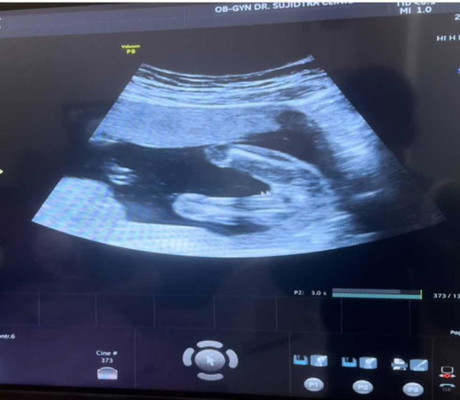

ช/ญ ค่ะแม่ๆ ซาวดูเพศ 17+3

ช่วยดูให้น่อยค่ะแม่ๆ ญ/ช

น่าจะผู้หญิงไหมคะเพราะจู๋ไม่โผล่

เหมือนเราเลย หมอบอก ผญ

สาวน้อยแน่ๆค่ะ